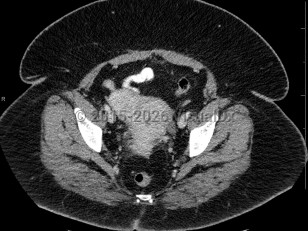

Pyelonephritis

Cystitis

Hydronephrosis

Renal calculus

Bladder cancerBladder cancer